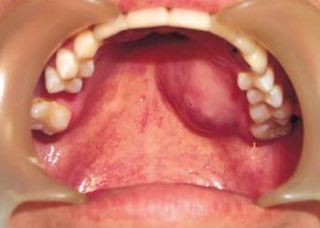

| Top: Ewing sarcoma of the thigh bone on a child's CT scan Bottom: Extraskeletal Ewing sarcoma of the hard palate | |

CT scan face- extraskeletal Ewing sarcoma hard palate